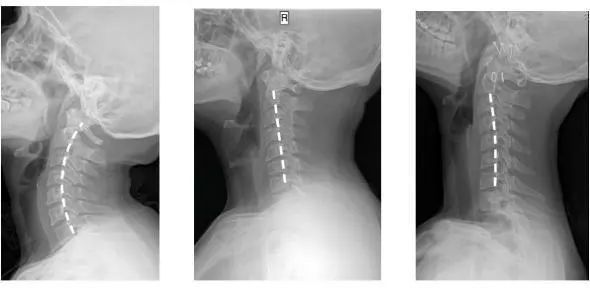

人正常的颈椎是有弧度的

大约是前凸30-45°

但随着颈椎长时间承受着巨大压力

过于疲劳状态

于是弧度就

逐渐退化 变直 甚至反弓

第一张为正常生理曲度,第二张曲度变直,第三张是反向弯曲

前凸的颈椎曲度被改变

结果就是引发椎间盘突出

造成对血管和神经的压迫

肩膀和脖子容易酸痛僵硬

这已是颈椎病的初期症状